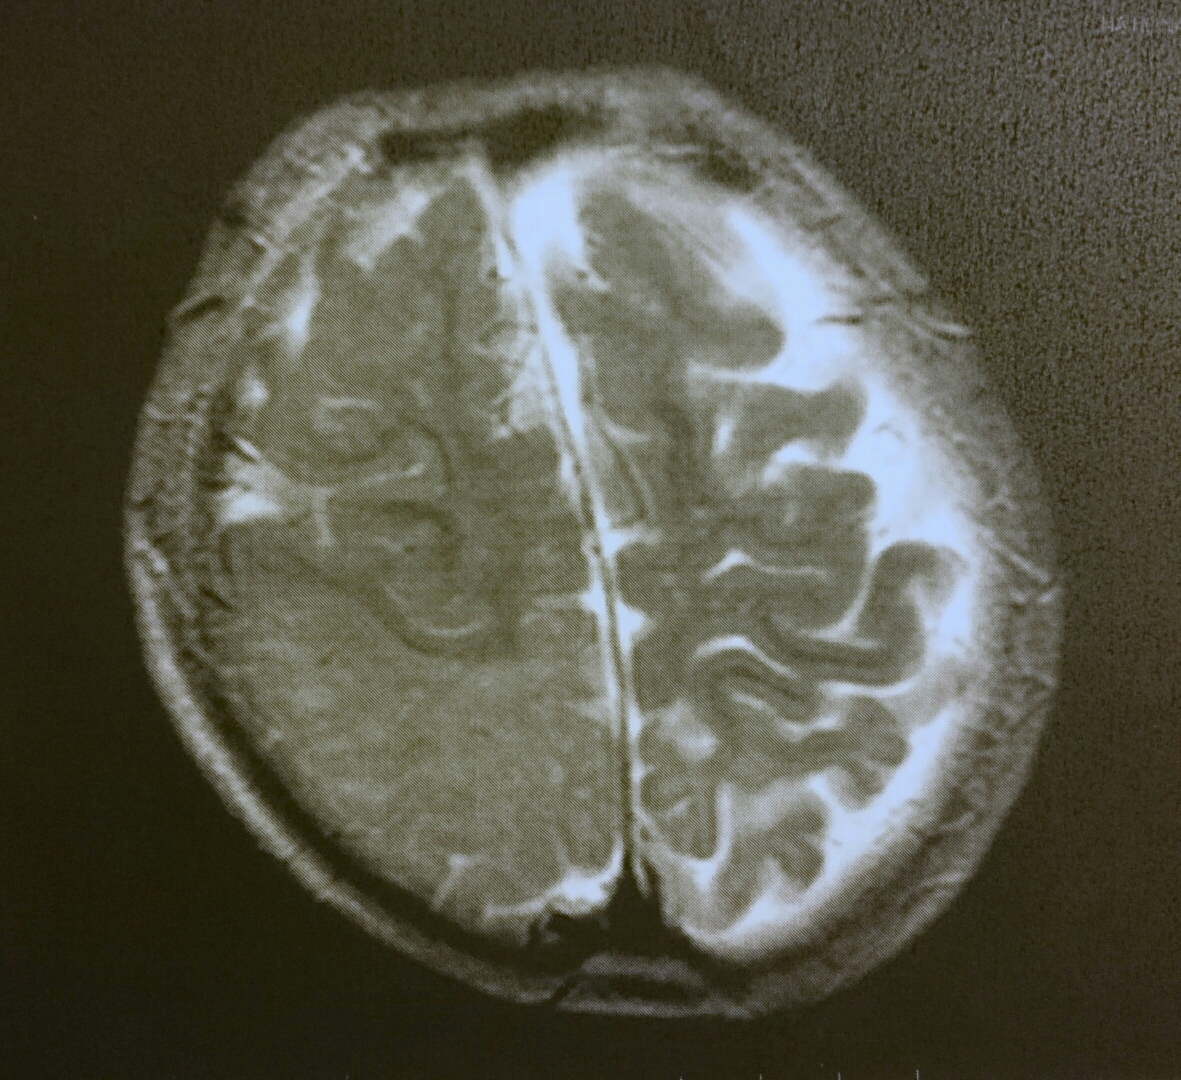

画像検査の結果、右脳の後頭部(写真左側の下半分)に、髄鞘化の異常が見つかりました。

(左下半分だけ色が薄く、皺の入り込みも少ないのが見てとれます)

ももぞうは多焦点で、外科治療には慎重にならなければならず、今までの検査では脳波所見と各種画像検査の結果が完全一致しきらず、外科治療には踏み切れませんでした。

ですが、今回の検査では脳がある程度成長してきたことで顕著な髄鞘化異常が目視でき、この異常はももぞうの脳波所見(発症時からずっと、一番大きな脳波異常は右後頭部にあります)と一致します。

もしまた再発した場合、今度は外科治療に踏み切れる可能性が大いにあるということです。